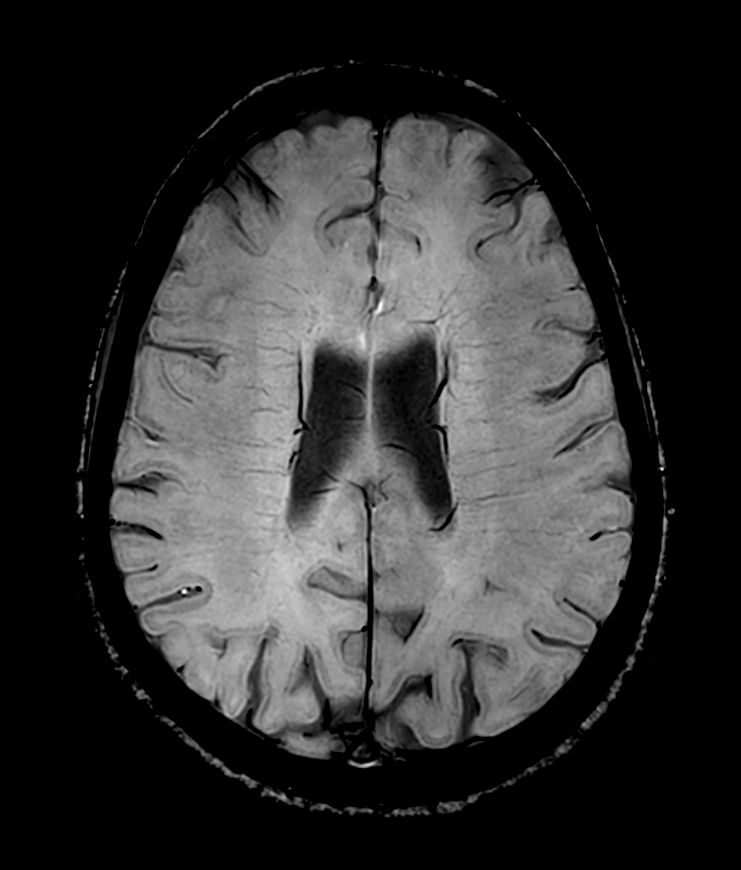

3D T2w FLAIR BrainVIEW Compressed SENSE